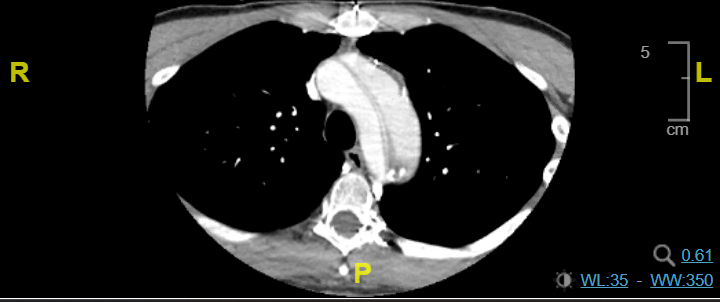

Case Presentation: A 42-year-old male with a history of hypertension and chronic Stanford type A/DeBakey I AD post aortic arch and valve repair (11 years prior), with thoracoabdominal dissection and aneurysmal changes, presented with difficulty in speech and unsteady gait. Blood pressure (BP) was 183/102 mmHg. ECG showed normal sinus rhythm. The last well-known was 45 minutes before the presentation; the National Institutes of Health stroke scale (NIHSS) was 6. The non-contrast CT head was unremarkable; CT angio showed left M2 MCA occlusion in the Sylvian fissure, Stanford type A AD with flaps crossing the origins of the brachiocephalic, left common carotid, and left subclavian. CT head perfusion revealed 65 cc of ischemic penumbra in the left MCA territory and a core infarct of 7 cc. MRI of the brain revealed an acute infarct in the left frontal and parietal lobes; CT chest/abdomen/pelvis showed an aneurysmal thoracoabdominal aorta (descending: 6x5.9 cm; suprarenal: 4.1x4 cm; infrarenal: 5.4x6.1 cm) with mural thrombus in the false lumen. On day 0, his mental status declined, NIHSS increased to 16 and he required intubation. He was taken for emergent percutaneous intracranial mechanical thrombectomy (MT) through left carotid artery access by vascular surgery, followed by interventional neurology rescue and achieved thrombolysis in cerebral ischemia score (TICI) 2C. He was extubated on day 1, and NIHSS improved to 3 over the next 3 days.